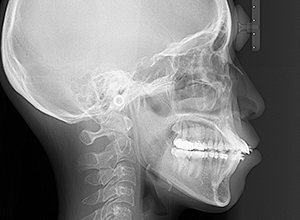

X-Ray

X-Ray所見

セファロ所見 下顎枝、骨体部共に大きくしっかりとしており下顎角は平均的であった。中顔面部の高さは高く奥行きあもり、上下顎骨は調和のとれた骨格形態をしていた。

パノラマ所見 右上8は埋伏していた。右下4根尖部付近にセメント質腫様所見が認められた。